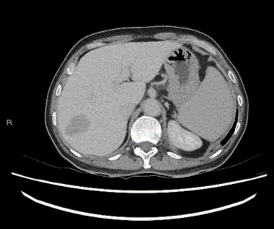

Figure 2C: Delayed phase of contrasted computed tomography scan of the liver, the lesion in segment VII remains hypodense relative to liver.

We proceeded with a computed tomography of the liver (CT liver) for further evaluation. CT liver showed a 4.3 x 2.4cm heterogeneously hypodense lobulated mass in segment VII of the liver. The mass was hypodense to the liver on all phases (plain, arterial, venous and delayed). There was mild heterogeneous enhancement, but there was no arterial enhancement (Figure 2A), washout (Figures 2B & 2C) or pseudo capsule, which should be expected in hepatocellular carcinoma. In view of the known history of thalassemia and the presence of paravertebral soft tissue masses that were likely to be extramedullary haematopoiesis, the possibility of extramedullary haematopoiesis was suggested. The other lesion was a 0.9cm hypodensity in segment VI of the liver, which was diagnosed as a flash-filling haemangioma. A magnetic resonance imaging (MRI) was then ordered for the indeterminate segment VII lesion. On MRI, the hepatic segment VII mass in question showed mild heterogeneous contrast enhancement but no appreciable arterial enhancement, washout or pseudo capsule (Figure 3A & Figure 3B).